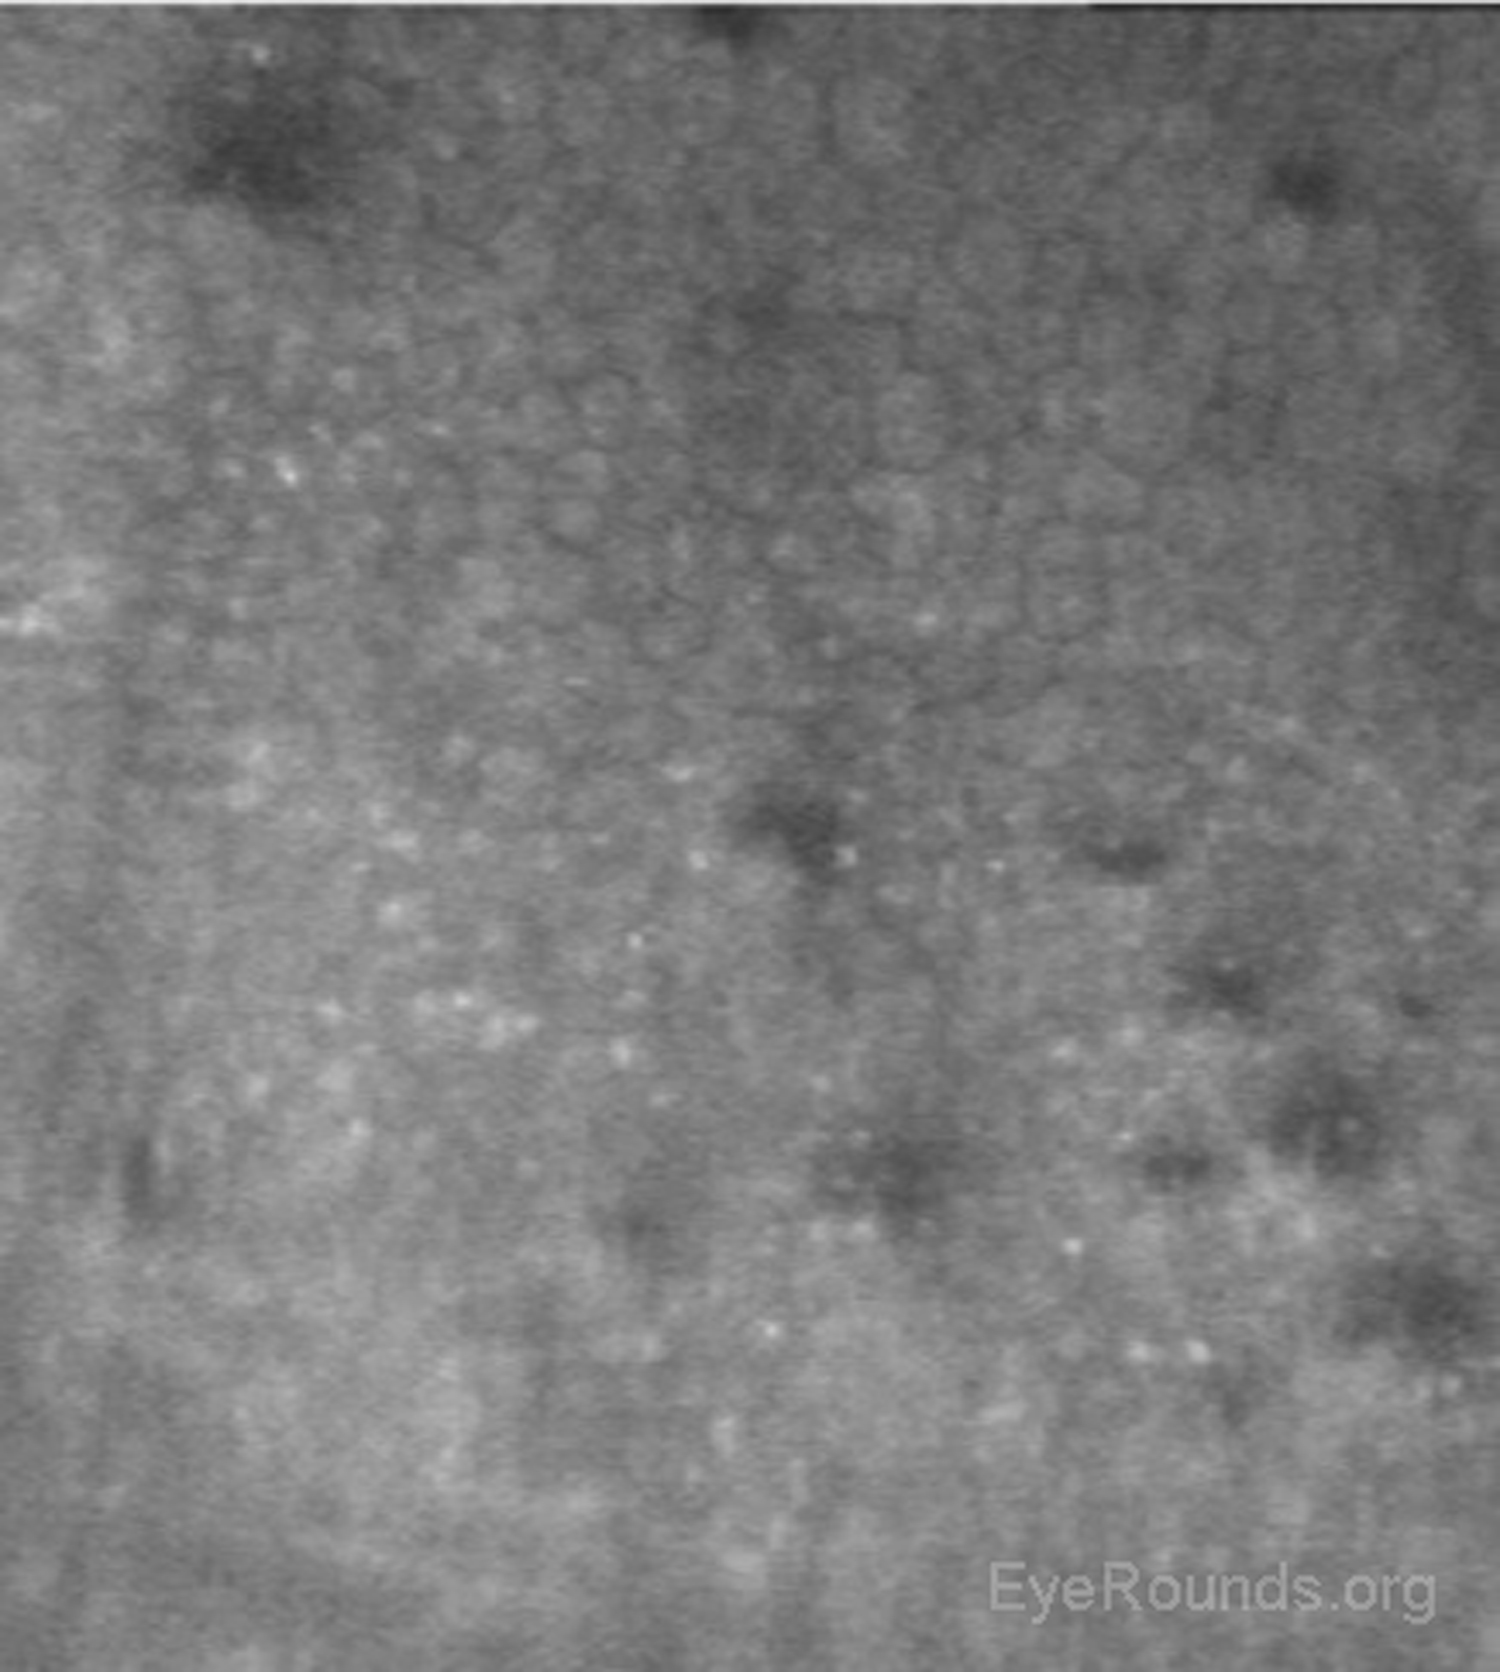

Confocal microscopy showing normal corneal endothelium

Figure 15. Confocal microscopy showing normal corneal endothelium. Note the small, hexagonal cells with minimal variation in cell size or shape.

When used to assess endothelial cell health, both qualitative inspection of the endothelium and quantitative assessment of the endothelial cell density must be performed. Normal endothelial cells should appear small, hexagonal, and uniform. Pleomorphism is the presence of high variation in cell shape, while polymegathism is variation in cell size. Endothelial cell density can be obtained automatically or by manual counting and is expressed as cells/mm2 (Figure 15).